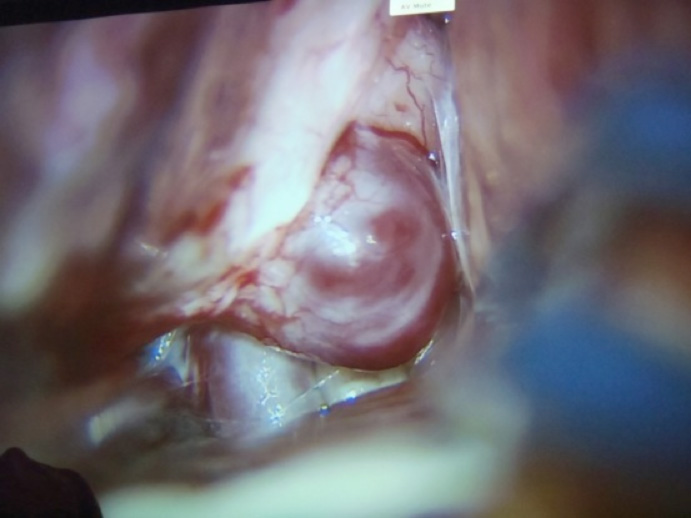

Aneurisma gigante paraclinoideo.